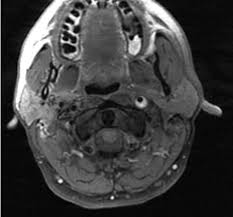

Carotid artery dissection (concept id: Each common carotid artery has an internal and an external branch. Carotid artery dissection is a tear in one of the layers of the artery wall. Spontaneous dissection of the carotid artery occurs in 3 per 100,000 of the population annually (1). It manifests with headache, neck pain, temporary vision loss, and/or ischemic stroke. This causes bleeding into the artery wall. Commonest in those in their mid 40s but seen at any age. Roller coasters are also a no no. Blood vessel walls normally have three layers, and a tear in any of these can allow blood to flow into the resulting space, causing the vessel to bulge. The first portion of each carotid artery is the called the common carotid artery. Carotid artery dissection is a major cause of cerebral infarction in the young. Mr signal of the mural hematoma has a similar temporal evolution than intracerebral counterpart. A carotid dissection can be due to injury.

The natural history of cerebrovascular fmd is unknown and management of symptomatic patients can be challenging. A carotid dissection is a tear in the inner layer of the wall of a carotid artery that allows bleeding into the artery wall. Internal carotid artery (ica) dissection, like arterial dissection elsewhere, is a result of blood entering the media through a tear in the intima 1 and is a common cause of stroke in younger patients. Carotid artery dissection has been described after chiropractic manipulation. It can involve a carotid or vertebral artery and sometimes multiple arteries can be involved.